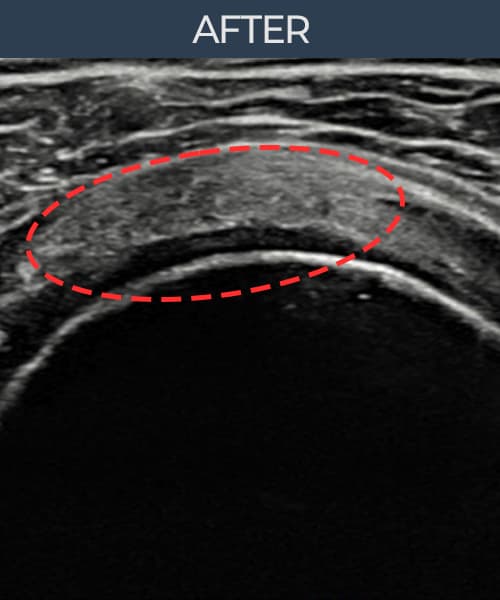

실제 환자의 시술 전후 초음파 영상입니다.

수술 없이 이뤄낸 회복을 직접 확인하세요.

모든 초음파 영상은 실제 환자의 동의를 받아 게시하였습니다. 개인차가 있으며 동일한 결과를 보장하지 않습니다.